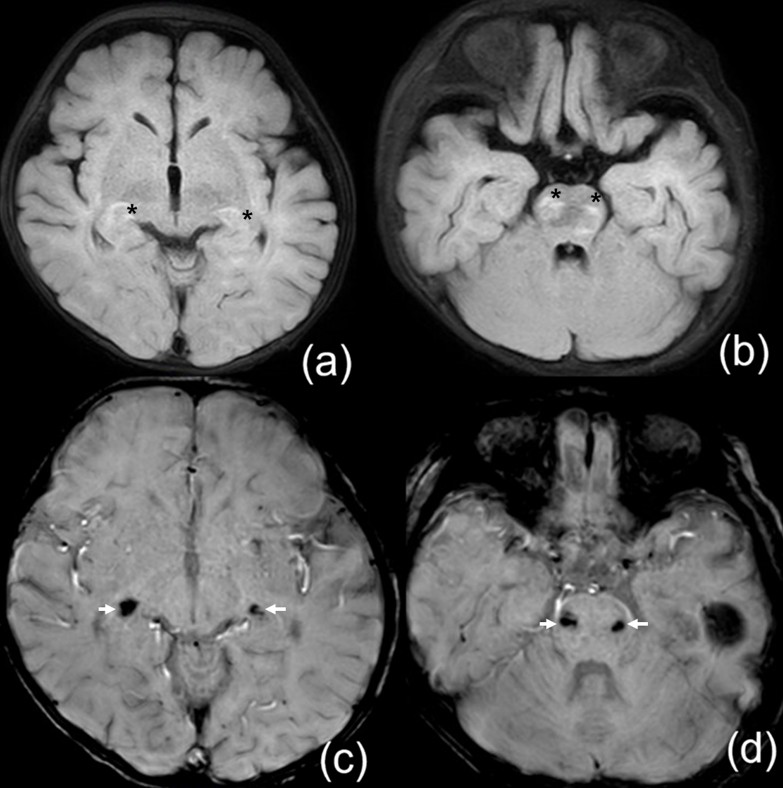

Acyclovir was administered to three patients (Patients 1, 18, 25; 16%). Only Patient 1 was classified as presumed HHV-6 infection, presenting with recurrent seizures and altered consciousness after 3 days of high fever. A rash developed on the fourth day. CSF pleocytosis was observed, and brain magnetic resonance imaging (MRI) revealed hyperintensity in the pons, midbrain, and bilateral lower thalami, accompanied by focal hemorrhage (Fig. 1.). Empirical treatment with acyclovir, antibiotics, and intravenous immunoglobulin (IVIG) was initiated for suspected encephalitis. HHV-6 infection was confirmed on hospital day 5, when the patient was already improving; therefore, acyclovir was maintained without switching to ganciclovir. The patient recovered without acute sequelae but later developed epilepsy. Patient 25 presented with fever lasting 5 days, headache, lethargy, and CSF pleocytosis, prompting empirical treatment with acyclovir under the impression of encephalitis. Enterovirus and HHV-6 were detected, but treatment was stopped because several features indicated enterovirus infection, including the concurrent seasonal outbreak, marked CSF pleocytosis (>1,000/µL), and rapid clinical improvement within 1–2 days. Patient 18 was admitted with prolonged fever of unknown origin. EBV, CMV, and HHV-6 were detected on multiplex PCR, and acyclovir was started due to suspected EBV infection supported by serology. The patient was transferred before outcome assessment.